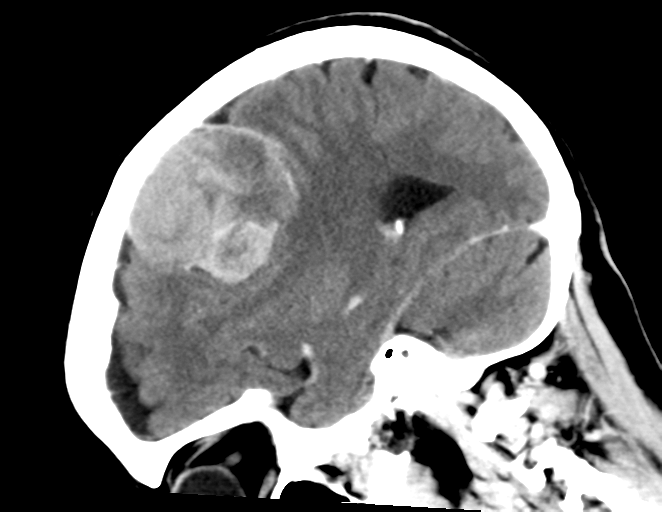

脑膜瘤是脑膜的肿瘤,脑膜是覆盖大脑和脊髓的膜。较常见的是良性脑膜瘤或I级脑膜瘤,它们很小,不会像癌性肿瘤一样无限期地生长。非典型脑膜瘤who二级,非典型脑膜瘤,也称为II级脑膜瘤,是一种脑膜瘤,在治疗或切除后可能会恶变并重新生长。Ⅲ级脑膜瘤会迅速生长,威胁到压缩邻近的脑组织并侵入骨骼。即使是良性脑膜瘤,由于其在大脑中也可能很危险。

脑膜瘤是脑肿瘤的较常见形式之一,约占全部此类癌症的30%。脑膜瘤的诊断通常是通过磁共振成像(MRI)进行的。有症状的患者将先接受神经系统检查,然后再进行脑成像以确定他们是否患有脑肿瘤。在无症状患者中,诊断有时会在需要其他医学投诉的脑部成像期间发生。

有症状的患者通常具有非典型或恶性变种。他们报告神经系统症状,例如头痛,癫痫发作,感觉丧失,恶心,视力模糊和对光敏感。它们几乎可以在神经系统中的任何地方发育,但是大多数脑膜瘤发生在头部,通常在脑干,颅底,静脉窦或视神经鞘附近。